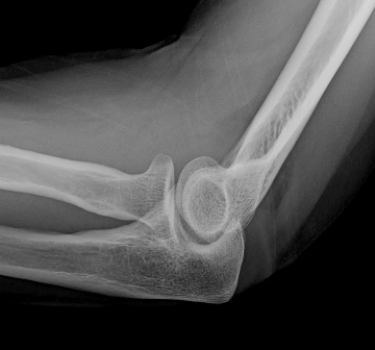

7

Lateral elbow radiograph after trauma; other radiographs show no fracture. Your diagnosis is:A) occult intra-articular fracture.

B) dislocated elbow.

C) normal elbow.

D) torn distal biceps tendon tour.